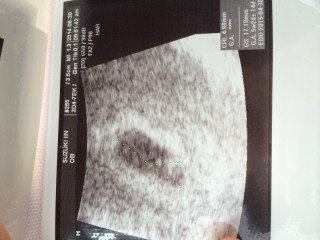

胎嚢10ミリ 赤ちゃん2.2ミリ

ちょっと小さいけど、成長しているから次回は心拍確認できるかなと言われました!

大きくなってね★